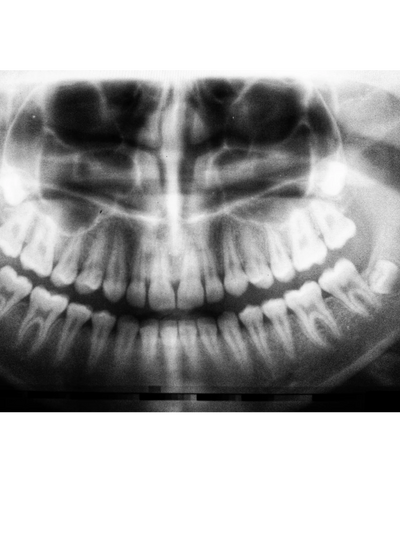

A panorex is a very impressive piece of imaging machinery because it is capable of identifying many issues and structures that a normal x-ray cannot. Initially, you will stand with your chin on a small ledge. Once positioned in the machine, it will rotate around your entire head taking a full 360- degree view of the teeth, head, sinuses, bones, and joints. The ability to view the full structure of your head as a whole is very informative to the dentist. It will allow the dentist to view your face as a whole. The panorex is very powerful tool that is capable of viewing specific types of structural problems, tumors, impacted wisdom teeth and the condition of TMJ.